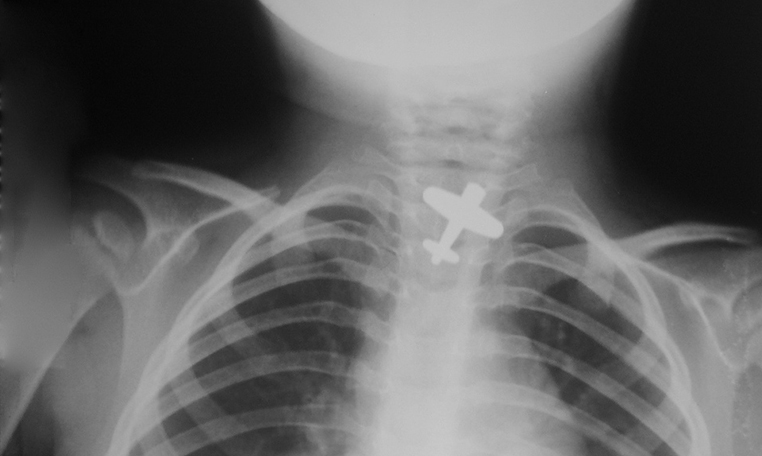

Cuerpo Extraño en Esofago